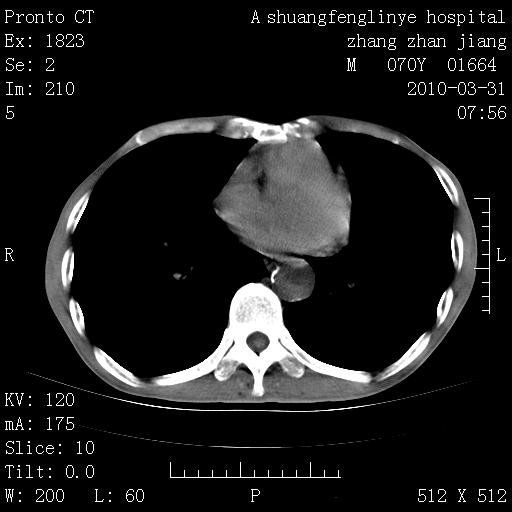

双上肺继发型tb并左上空洞形成,主动脉冠脉钙化。

1)两肺上叶继发性肺结核并左肺上叶空洞形成。2)冠状动脉及主动脉钙化。